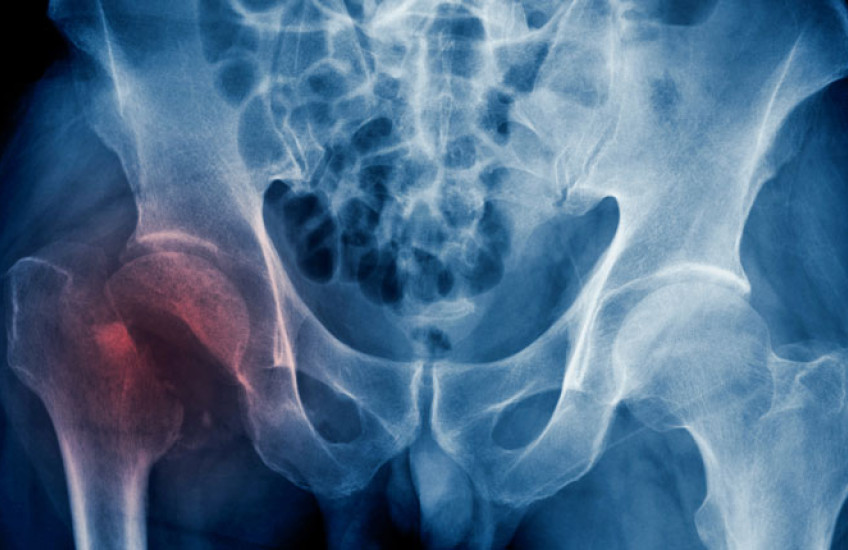

An international study that included researchers from Harvard Medical School indicates that while age- and sex-standardized hip fracture incidence rates have decreased in most regions around the globe, the number of hip fractures worldwide is projected to nearly double by 2050, compared to 2018.

Hip fracture remains a global public health concern contributing to increased dependency, morbidity, and mortality and placing a burden on patients, their families, and health care systems.